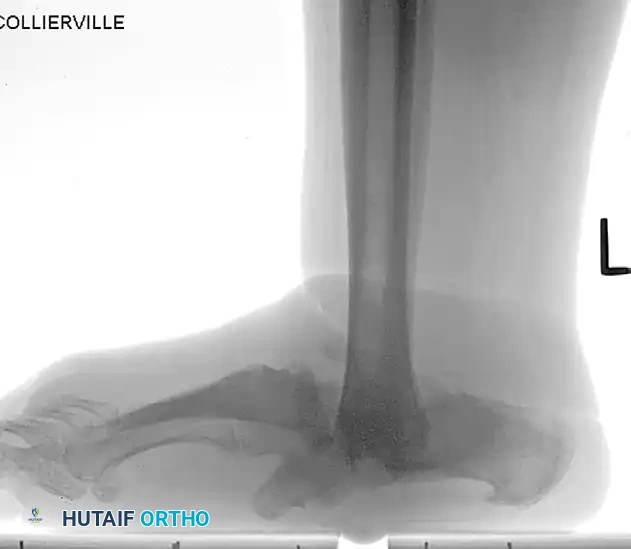

The following preoperative and postoperative radiographs demonstrate the successful application of augmented fixation in a young diabetic patient with a severe bimalleolar fracture-subluxation:

FIGURE 85-25 A and B: Preoperative radiographs of a highly unstable bimalleolar ankle fracture-subluxation in a 19-year-old man with a 12-year history of insulin-dependent diabetes mellitus.